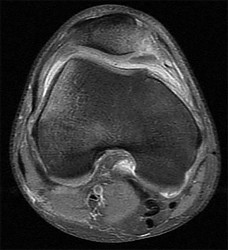

Question 3:

A 15-year-old male presents with worsening knee pain. Radiographs reveal a metaphyseal aggressive bone lesion with a 'sunburst' periosteal reaction and Codman's triangle. Biopsy confirms a high-grade intramedullary osteosarcoma. What is the standard algorithmic approach to treatment for this patient?

Correct Answer: Neoadjuvant chemotherapy followed by wide surgical resection and adjuvant chemotherapy

The standard of care for high-grade classic intramedullary osteosarcoma is neoadjuvant (pre-operative) chemotherapy, followed by wide surgical resection (either limb salvage or amputation), and then adjuvant (post-operative) chemotherapy. The percentage of histologic necrosis seen in the resected specimen after neoadjuvant chemotherapy is one of the strongest prognostic indicators for long-term survival.